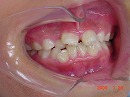

今回はこどもの歯並びの悪い(上下額が小さく、咬み合わせが低い)症例の治療法を紹介します。

9月歳3か月 女子

初診時乳臼歯にレジンを盛る事で咬み合わせの高さを治療していきます。

初診時